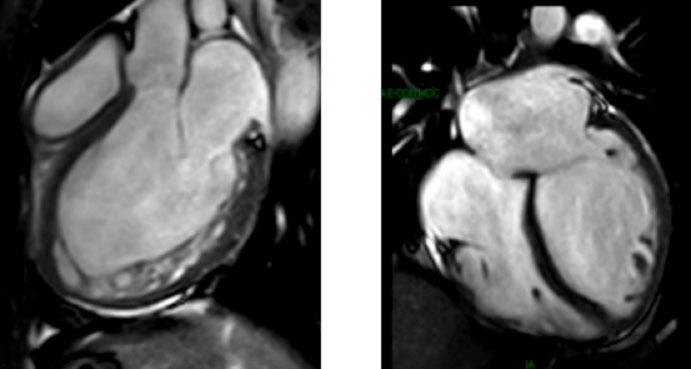

Il primo esame in caso di sospetto di MNC è l’ecocardiografia, che mostra aumentata trabecolatura delle pareti del ventricolo sinistro. La esatta definizione della malattia viene effettuata con la risonanza magnetica cardiaca, che permette di conoscere i rapporti fra miocardio non compatto, che di solito e prevalente nella parete basale e postero laterale del miocardio, e il miocardio contrattile. La RMNC deve essere ripetuta negli anni per cogliere l’evoluzione della malattia, in particolare il rapporto fra miocardio non compatto e miocardio contrattile.